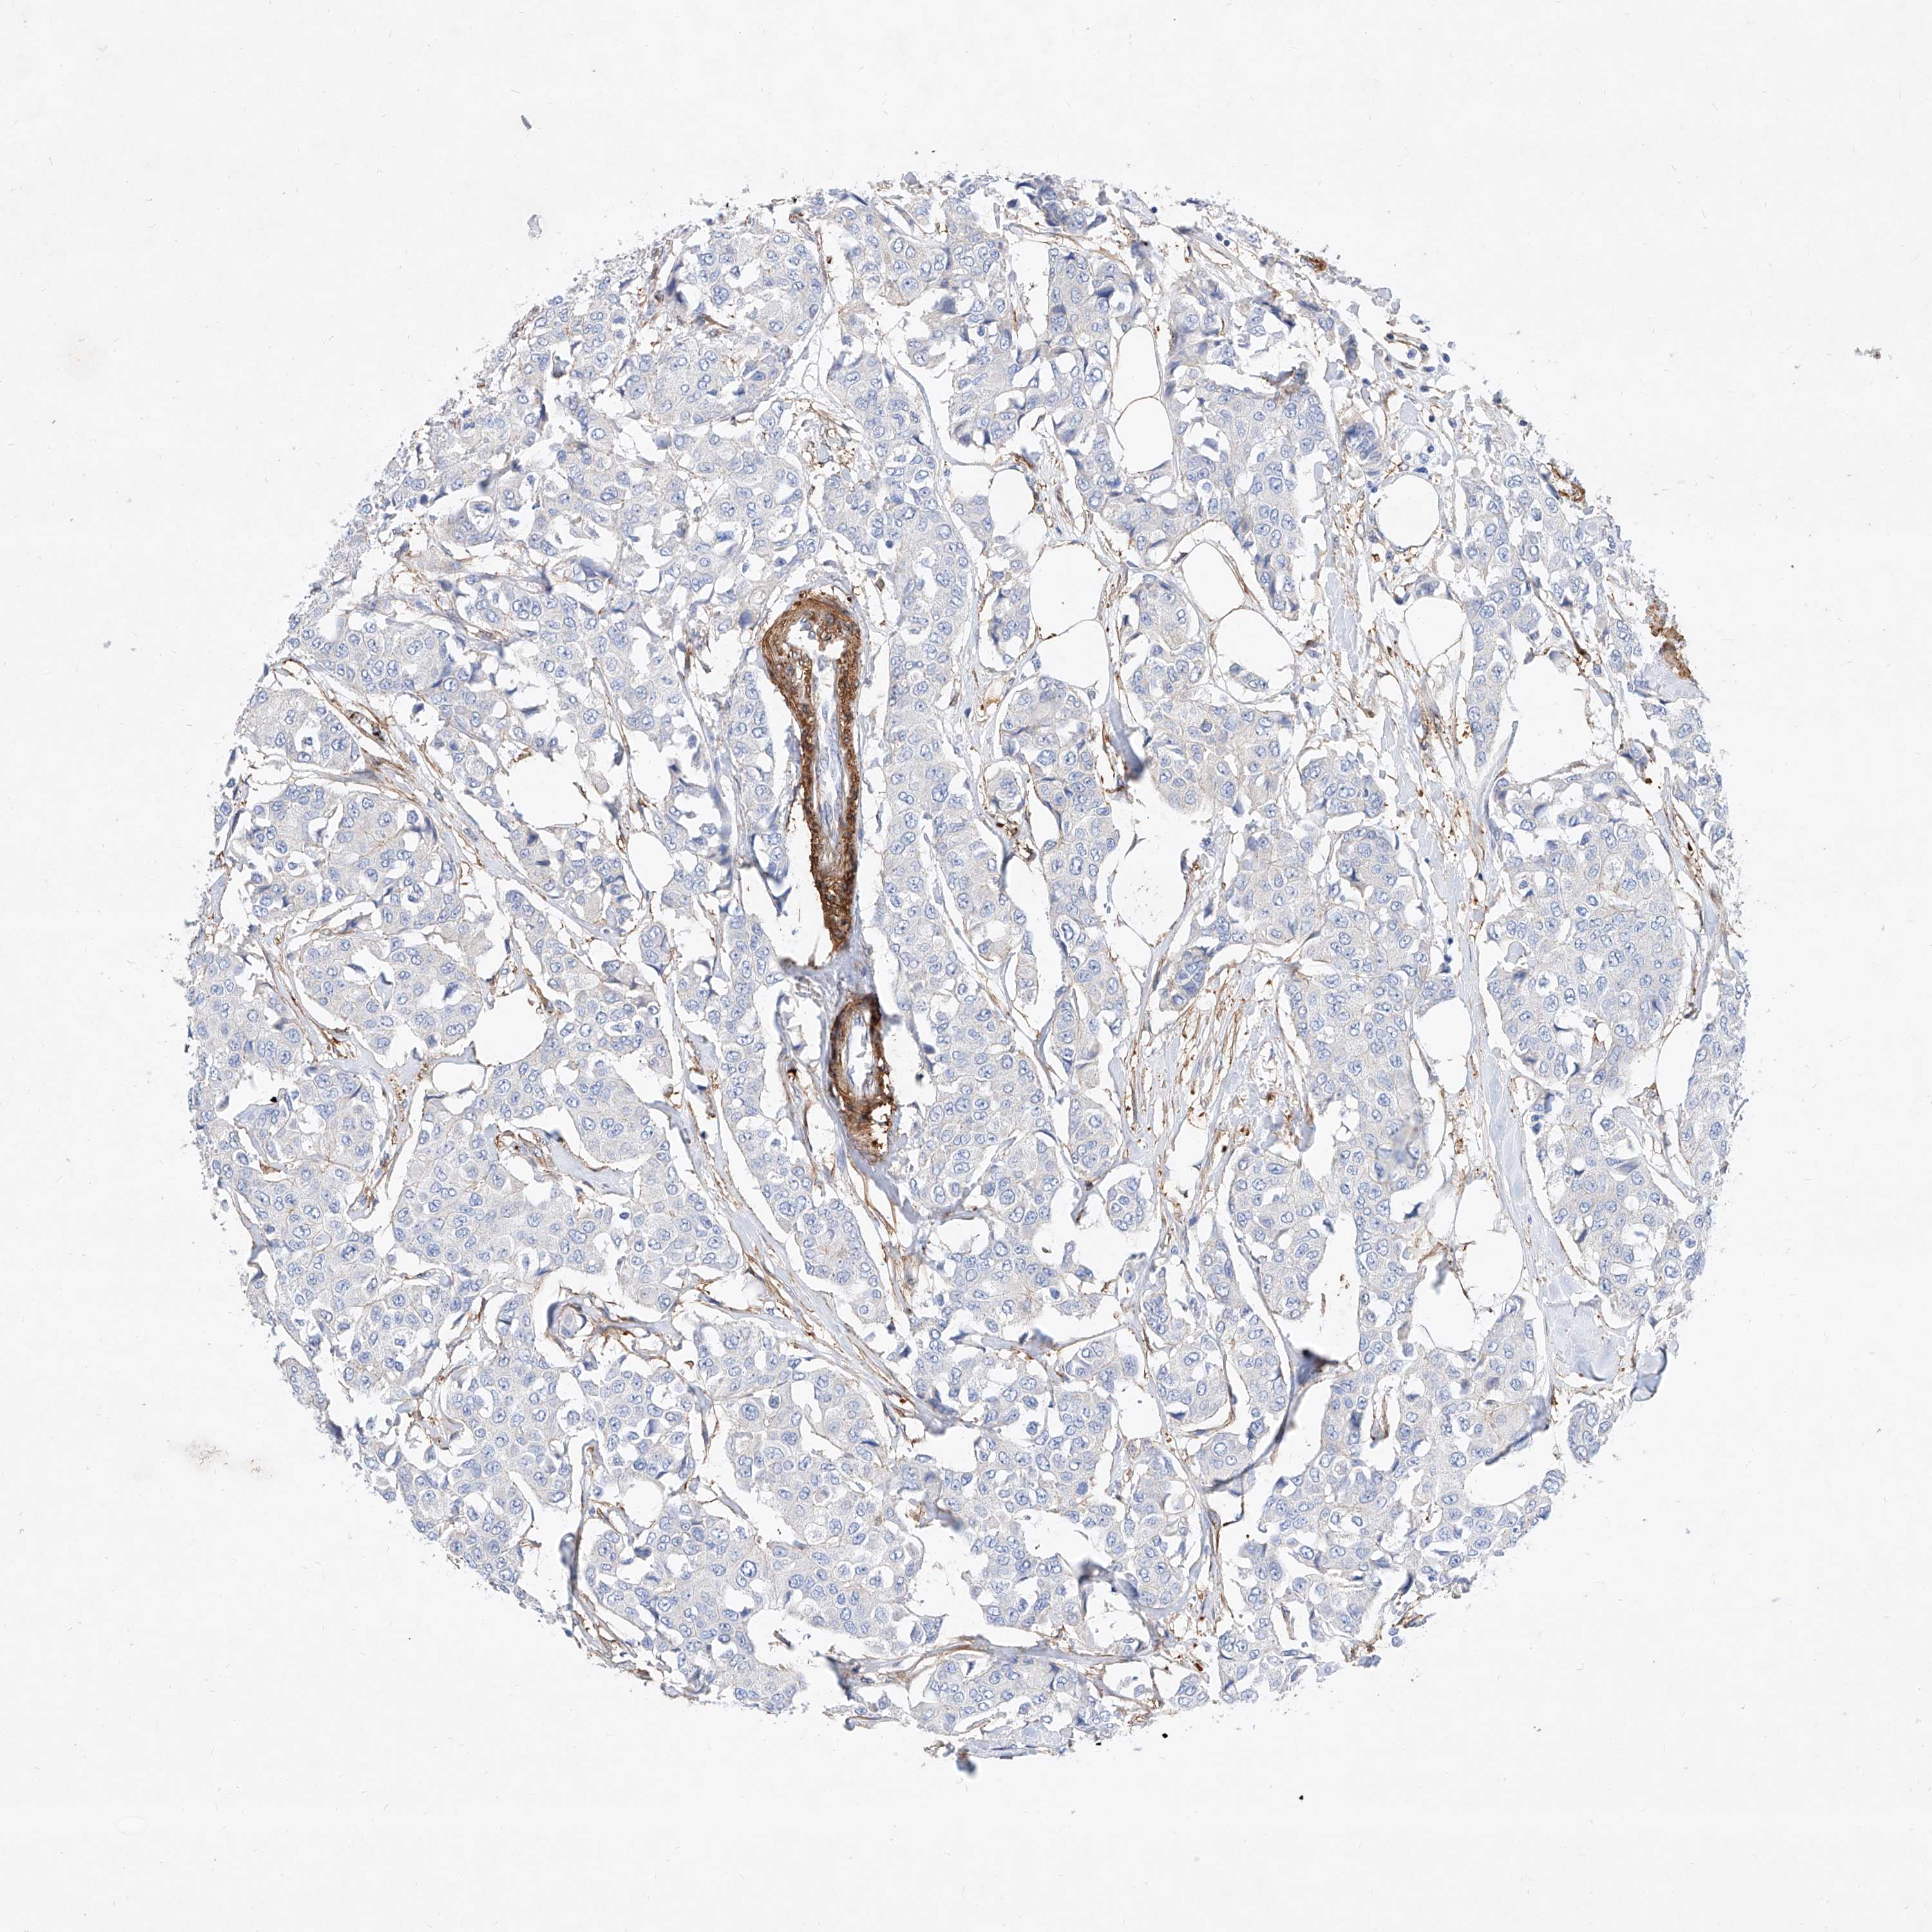

CANCER BREAST CANCER Show tissue menu

BRCA TCGA BRCA VALIDATION PROTEIN EXPRESSION